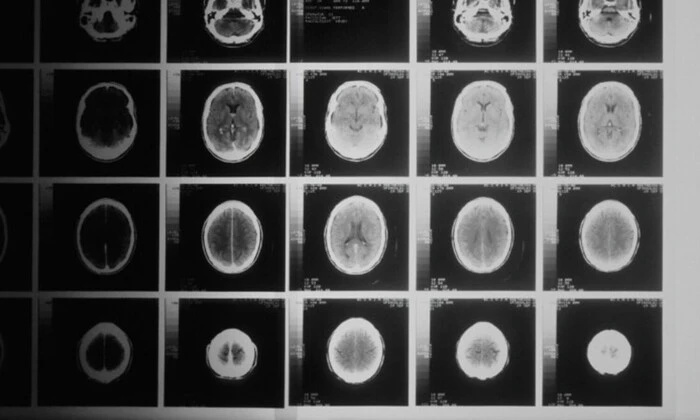

Компанія Microsoft розробила систему штучного інтелекту (ШІ) для медичної діагностики, яка може асистувати або навіть заміняти лікарів, вирішуючи складні випадки. Інструмент під назвою Microsoft AI Diagnostic Orchestrator (MAI-DxO) був створений підрозділом Microsoft AI за керівництва Мустафи Сулеймана, співзасновника DeepMind. MAI-DxO включає в себе віртуальний консиліум з п'яти ШІ-агентів, які діють як лікарі різних спеціалізацій. Ці агенти взаємодіють, обговорюють варіанти та разом надають висновок. Систему протестували на 304 складних клінічних випадках з New England Journal of Medicine, результати були дуже вражаючі. Financial Times повідомив, що "агенти взаємодіють, обговорюють варіанти та колегіально формулюють висновок." Тестування використовувало нову методологію 'ланцюжка дебатів', що забезпечує прозорість логіки алгоритму. Найефективніша модель у тестуванні - o3 від OpenAI, яка правильно розв'язала 85.5% медичних завдань, що значно зекономило кошти. Систему можна інтегрувати в продукти Microsoft, які щодня обробляють масу медичних запитів. Співробітники компанії зазначили, що їхня мета - створити ШІ, яка перевершує людину за швидкістю, точністю та економічністю. Мустафа Сулейман заявив, що "ми наближаємося до створення ШІ, яка значно перевершить людину за швидкістю, точністю та економічністю." Домінік Кінг, колишній керівник DeepMind, тепер співробітник Microsoft, відзначив потенційну ефективність нової системи в галузі охорони здоров'я, але закликав до додаткових тестів перед широким застосуванням. Також було зафіксовано першу успішну операцію з пересадки серця за допомогою робота в США у Baylor St. Luke's Medical Center, де 45-річний чоловік із серцевою недостатністю отримав новий орган.